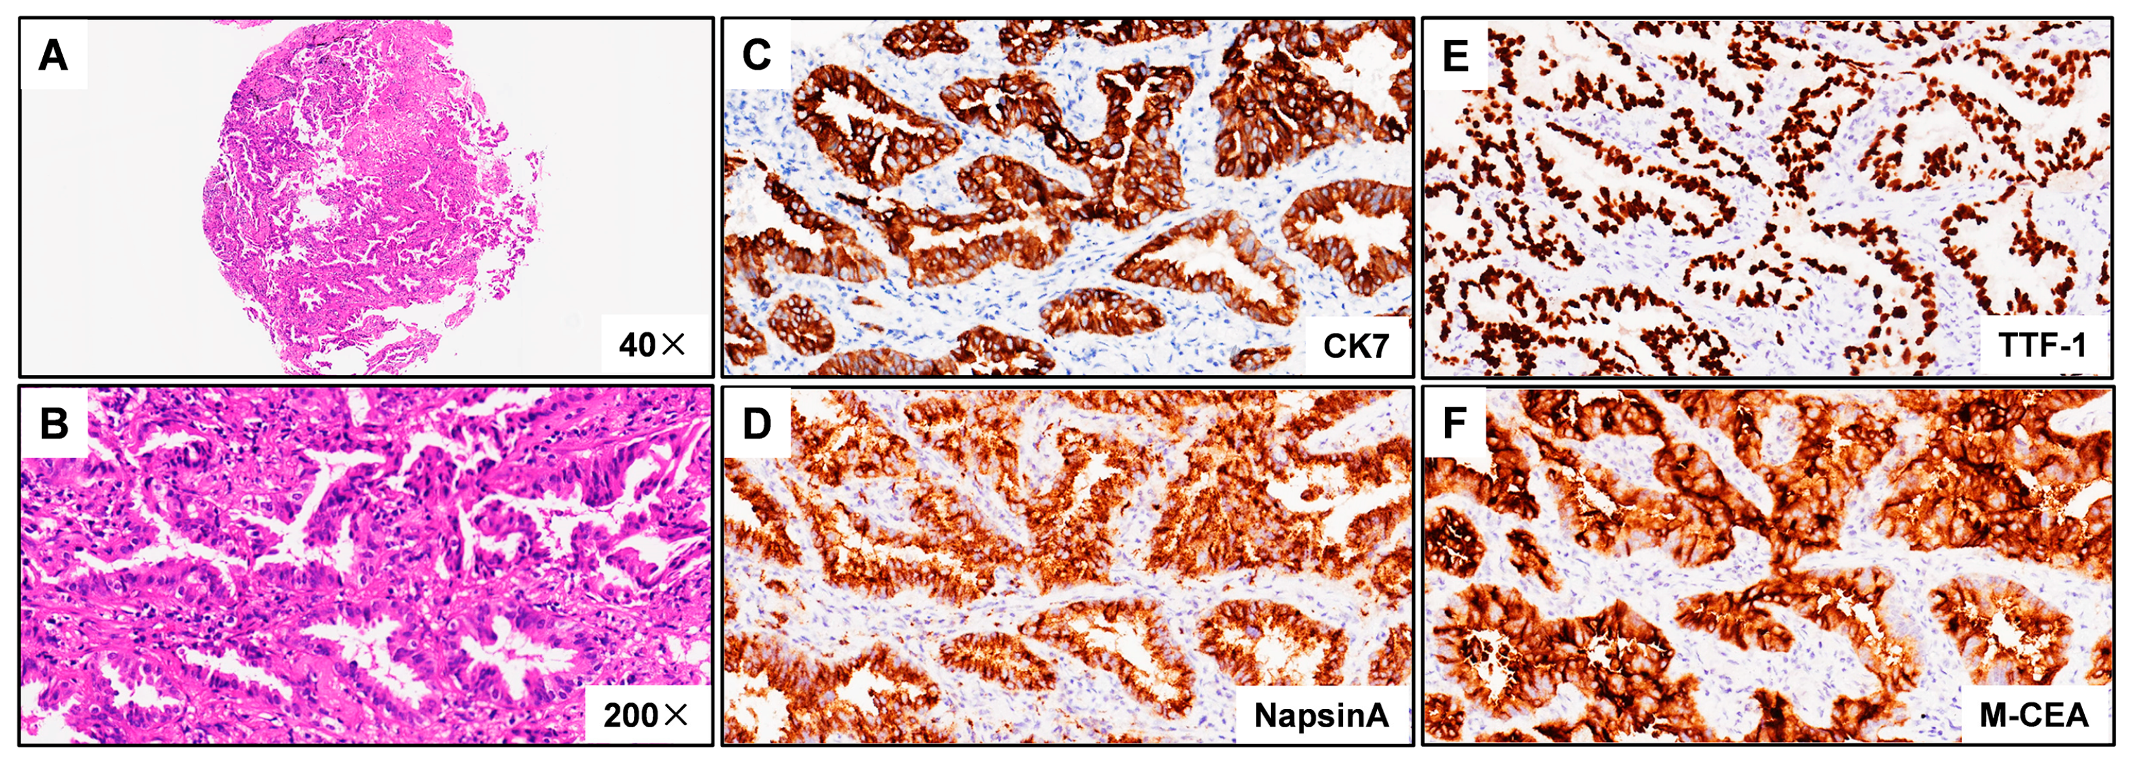

3.1. Case Description